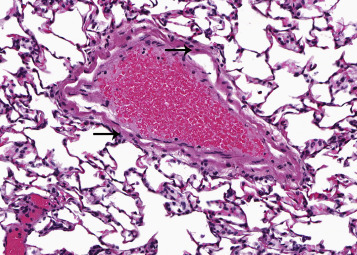

In the rat lung, veins of all sizes have an internal subendothelial thin layer of smooth muscle and an external layer of striated cardiac muscle which is continuous with the myocardium of the left atrium (Figure 23.6 ). The cardiac muscle around the pulmonary vein is arranged as an internal circular layer and an external longitudinal layer. There is great variation in the number of layers of cardiac muscle around the pulmonary vein. The external longitudinal layers extend further than the circular muscle layer. The cardiac muscle is present in the axial vein and its primary branches closer to the hilum. As the pulmonary vein branch and go deeper, they lose cardiac muscle layer (Almeida et al., 1975, Hosoyamada et al., 2010). Disease processes that affect cardiac muscle can affect that of the pulmonary veins as well. With acute myocarditis, for example, there may also be inflammation of the cardiac muscle in the pulmonary veins.

Figure 23.6.

Myocardial cells (arrows) surrounding a pulmonary vein.